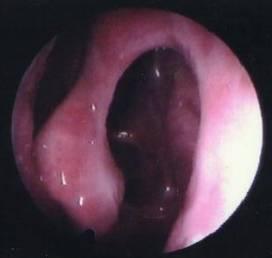

1、内镜检查:来源于中鼻道、嗅裂的黏脓性分泌物,中鼻道粘膜充血、水肿或有鼻息肉。

• 鼻腔检查:前鼻镜、鼻内窥镜。

图1中鼻道息肉